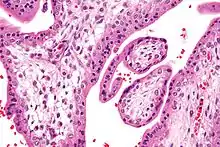

Histopathology of a chorionic villus, in a tubal pregnancy.

The bulk of the villi consist of connective tissues that contain blood vessels. Most of the cells in the connective tissue core of the villi are fibroblasts. Macrophages known as Hofbauer cells are also present.